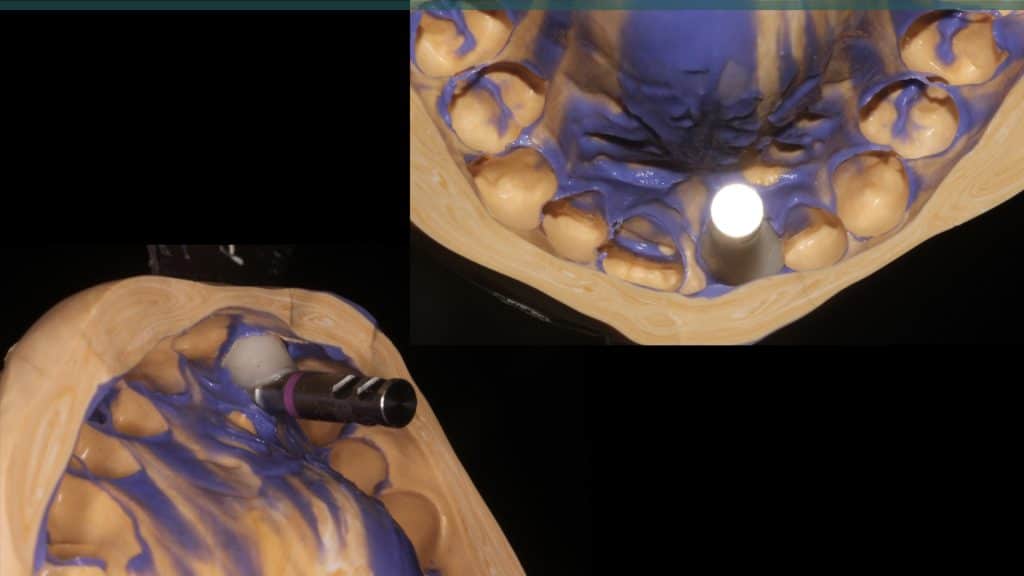

Occlusal check